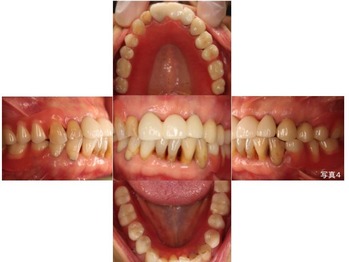

以下が治療後です。

18写真3

欠損部にはノンクラスプ デンチャーを作製しました。

18写真4